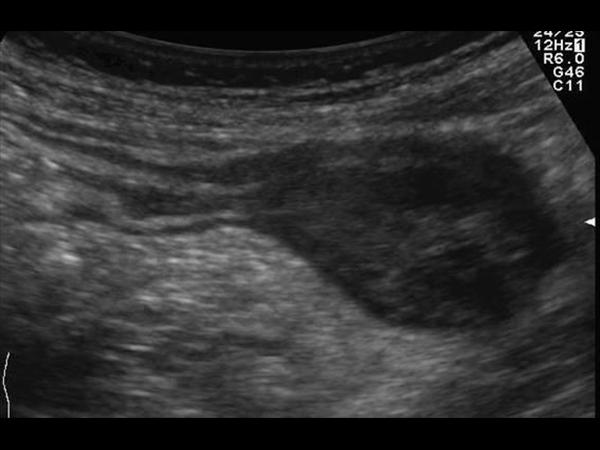

Mucocele ruột thừa

» Thông tin: Nam giới – 71 tuổi.

» Lâm sàng: Đau hố chậu phải mạn tính.